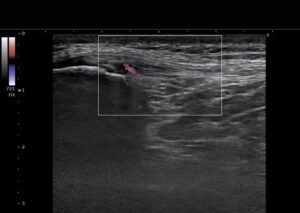

当院では最新鋭の超音波エコー観察装置を使用し、患部の状態をリアルタイムでチェックします。今回のケースで威力を発揮したのが**「ドップラー機能」**です。

組織内の血流の動きをカラーで表示する機能です。通常、健康な靭帯には血流はほとんど見られませんが、強い炎症が起きている場所や、損傷を修復しようとして異常な血管が増えている場所には、赤い信号(ドップラー信号)が強く現れます。

いわば、「今まさに燃えている痛みの火種」を視覚化する技術です。

今回のエコー検査でも、膝蓋靭帯の付着部にハッキリとした炎症反応を確認。選手本人も「あ、ここが原因だったんですね」と、自分の痛みの正体をモニター越しに納得されていました。